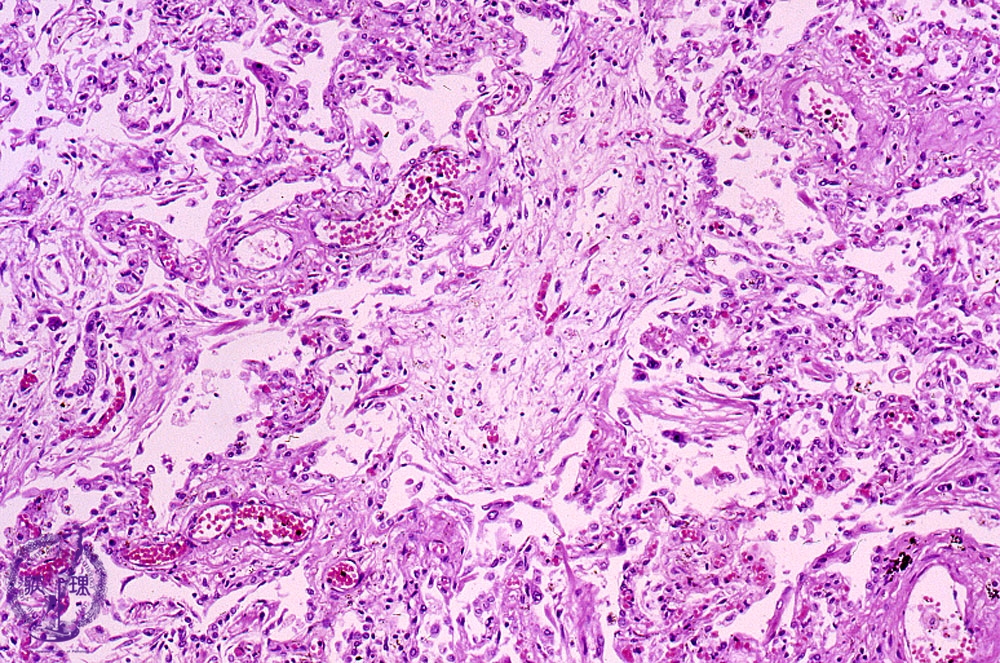

Microscopic view (HE stain, intermediate power view): Within the affected bronchiolar lumen, polypoid granulation tissue (Masson body, dotted line) is seen.